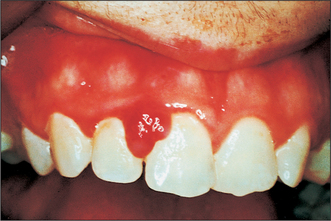

Colour

Colour will distinguish between fibroepithelial polyps (pink) (Fig. 8.1) and the white rough cauliflower presentation of viral papillomas (warts) (Fig. 8.2). Mucous cysts tend to be translucent with a bluish colour (see Figs 14.7, 14.8) and haemangiomas and ‘venous lakes’ (Fig. 8.3) dark blue. Pyogenic granulomas (Fig. 8.4) and giant-cell epulides (Fig. 8.5) normally present as maroon/red.

Fig. 8.4 Pyogenic granuloma.